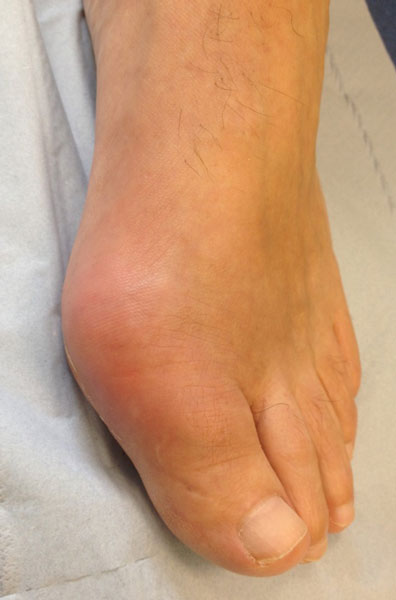

Although radiographic changes are usually a late feature, occasionally they may be seen at presentation, see figure 1. The most common presentation is a gout flare, characterised by acute onset of one, or occasionally more, hot, red, swollen joints which are extremely painful and exquisitely tender. Flares reach a peak in just 12-24 hours. Although any joint can be affected, most flares affect joints in the feet, knees, hands or elbows. Involvement of the first metatarso-phalangeal joint, termed podagra (seizing the foot), is very characteristic, see figure 2.